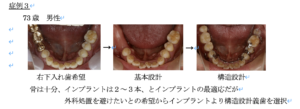

症例3